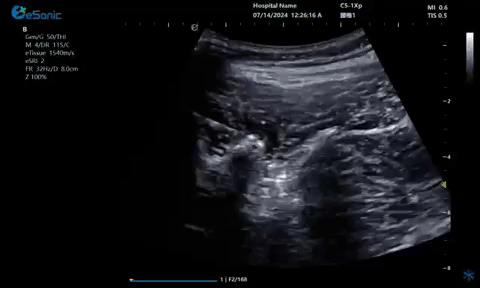

7月12—14日,中国医师协会2024年疼痛科医师年会在山东青岛圆满落幕。大会云集了国内疼痛领域诸多杰出专家学者,大家齐聚一堂,深入研讨疼痛医学领域的最新研究成就与临床实践心得,共同推动学术进步与临床发展。3377体育医疗(ESI)携eHertz系列产品亮相本次大会,凭借国内领先的超声技术和新型“E超”设备成功出圈,展位前吸引了众多访客驻足垂询。该系列产品凭借独特的功能集成,显著提升了设备的精准度和检查效率,为疼痛康复医疗的临床应用提供了全面完善的超声解决方案。值得一提的是,产品应用的穿刺针智能Map技术能够精准和高效的引导医生进行穿刺,既显著提升了医生的工作效率,同时也为患者提供了更优质的医疗服务。

疼痛康复领域中的肌骨超声应用,旨在实现对肌肉、肌腱、韧带、关节、神经、血管、筋膜、滑膜、滑囊、骨膜等组织结构的精确诊断评估。由于超声高频探头对上述机体组织的细微结构具有优异的分辨率,因此能够更为明确地评估这些组织的损伤和炎症状态。同时,超声设备的实时动态评估能力,使得对运动中的相关疾患也能进行准确的评估,这是其他诊断设备所不具备的优势。在康复治疗过程中,肌骨超声还用于介入穿刺治疗,如外周神经阻滞(PNB)、小关节注射、肌筋膜松解术、封闭、小针刀、冲击波治疗等。在超声引导下,这些治疗操作实现了可视化,从而真正意义上实现了精准医疗。以PNB为例,作为一种局部用药方式,其对患者全身干扰小,药物副作用少,且费用较低,因此仍然是临床治疗疼痛的主要方式之一近年来,超声技术在临床康复领域的应用日益凸显其优势。相较于传统的盲穿技术,超声引导下的PNB能够直观显示穿刺和注药过程,无需患者表达异感,避免了反复穿刺给患者带来的痛苦。这种技术显著提高了外周神经阻滞、静脉穿刺的成功率、精确性和安全性,同时减少了不良反应和并发症的发生,为患者带来了福音也相信在不久的将来,eHertz系列产品将会在全球医疗市场上掀起一场技术革新的风暴,让更多的人受益于我国医疗技术的进步。